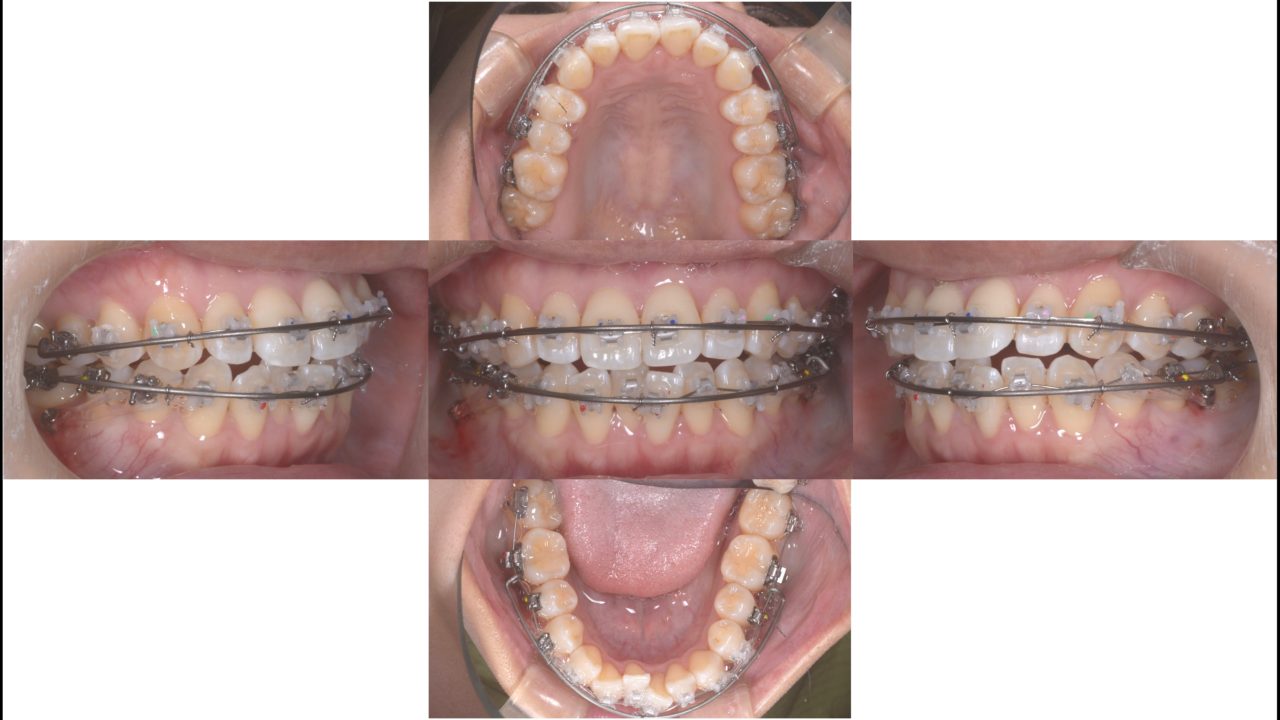

矯正治療開始 2019.6.28

マルチブラケットを上下顎に装着しました。歯は抜いていません。凸凹を治すためにマリガンオーバーレイアーチで側方拡大を行います。

開始5か月 2019.11.19

予定通り、5か月でほぼ前歯の凸凹は治りました。しかし、前歯がきれいになると口元をもっと引っ込めたいという希望が出てきました。治療計画を一部変更して、矯正用アンカースクリューを使い、上下顎の歯すべてを後方へ移動させる計画を入れました。